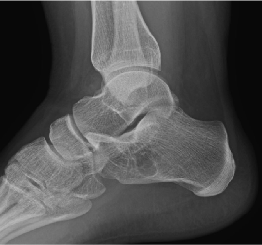

I performed a yet unpublished review of all the calcaneal bone cysts (33 cases) seen over the past 6 years at Ft. Leonard Wood (Table 1). I found only one study that had more cases, with 47 in their series.1 My series had ages ranging from 8–66 years. The majority were athletes in some form, either teenagers in high school, military recruits, or active duty soldiers. Twenty-seven of the 33 were in the military. Only 2 patients actually presented with persistent heel pain and one had a pathologic fracture. All the rest were diagnosed simply because they were being X-rayed for some other condition: bunions, ankle sprain, flat feet, etc. Most tumors of the foot are found incidentally on imaging and are benign per Temple and Pruza in 2021.2 Amazingly, none of the 33 presented with plantar fasciitis with the lesions ranging from a small cyst to something quite large as shown in Figure 1. Of the 33, only 3 patients required calcaneal bone curettage and grafting. Many of the larger lesions that involved trainees who were medically discharged from service.

A 15-year-old female athlete—softball, basketball, and volleyball—presented with hallux valgus and an asymptomatic bone cyst (Figure 2 and Figure 3). The patient underwent MRI evaluation (the MRIs were not available for this article). MRI revealed a fluid filled aneurysmal bone cyst involved almost the entire calcaneal body from medial to lateral. As the X-rays show, the lesion is a classic neutral triangle area with expansive size.